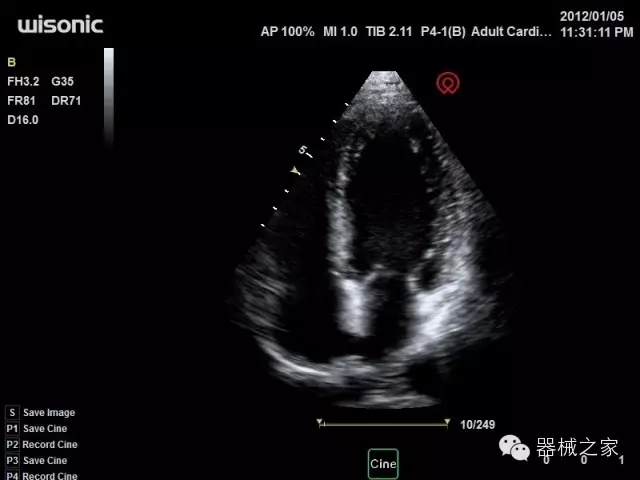

·飛依諾特有心臟純凈波探頭提供更好的穿透力和彩色敏感度,以及結(jié)合TView梯形拓展改善困難病人深部組織成像;

·獨有RF敏感血流使得心臟血流完美呈現(xiàn);